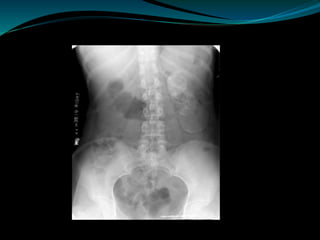

Plain Radiograph

 50% of patients may show positive findings on chest

radiograph.

 Disparity in renal size on plain films may indicate early

increase in size of the affected kidney due to caseous

lesions or a shrunken fibrotic kidney of

autonephrectomy. Calcifications are seen in 30% to

50% of cases.

 Focal calcifications occur within the caseating

lesions(pseudocalculi) .

 A characteristic diffuse, uniform, extensive

parenchymal calcification,

 Calculi may also be seen in the collecting system or

ureter secondary to stricture formation.

 Calcifications of the prostate and seminal vesicles

are seen in 10% of cases.